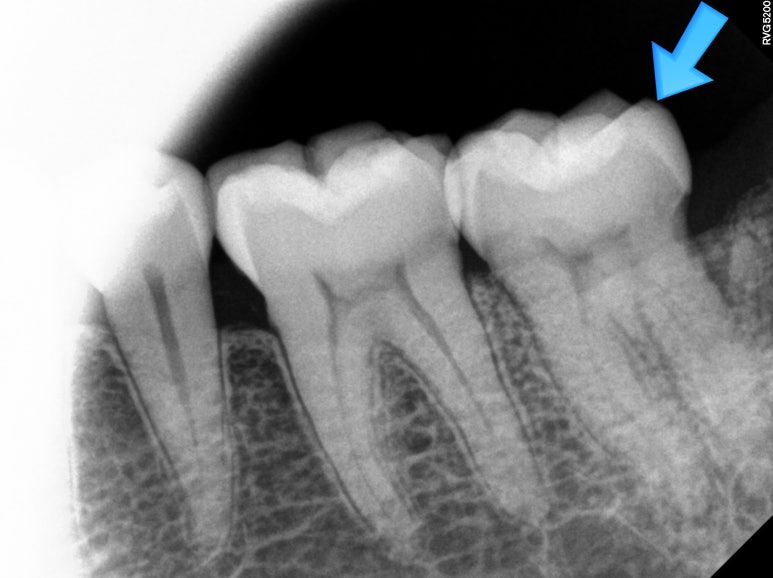

불편하다고 얘기하셔서 아까 파란색으로 표시했던 왼쪽 아래 어금니를 자세히 살펴보기 위해 치근단사진 촬영을 해보았습니다.

분명히 명확한 충치나 잇몸질환은 관찰되지 않았어요...

그렇지만, 치료 후에도 환자분은 씹을 때 찌릿한 통증을 호소하셨고.. 1-2달 기다려보았지만 개선되지 않았습니다.

Crack tooth 구나!